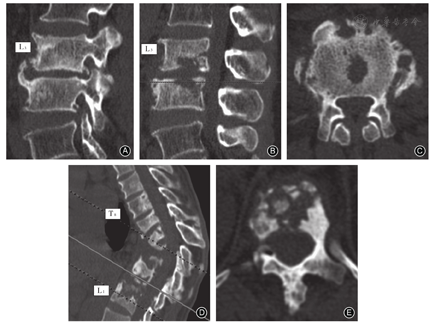

布鲁杆菌性脊柱炎CT主要表现为骨小粱粗大、紊乱,结构不清,椎体边缘骨质增生变尖,破坏灶边缘有程度不等的硬化,病灶邻近椎体的骨密度普遍增高,但不出现死骨,且椎弓根无破坏。病变椎体的骨膜肥厚,增生的骨刺、骨赘向椎体边缘突出,虫蚀样骨破坏伴增生硬化在CT中表现为"花边椎"、"鹦鹉嘴"[2,22](图1A,图3A)。前纵韧带及棘间韧带钙化,严重时有骨桥形成,这种椎体破坏伴有明显的增生性反应,骨质修复反应特别强烈。椎旁脓肿的软组织影均与椎体破坏区相连,形态不规则,界限清楚,推压邻近的腰大肌,极少出现寒性脓肿(表5)[9,23]。

对于脊柱结核,CT可更早发现异常,在确定骨破坏程度、后柱受累、关节病变、关节受累和局部稳定性方面非常有价值[24]。CT检查可将骨破坏分为四种类型,骨碎片型:椎体破坏后留的小碎骨片或(和)椎旁的小钙化灶,或椎体成为多个碎片,密度不均,有"满天星"样死骨渣散在其中(图1B,图3B);溶骨型:椎体内或前方形成局限性溶骨性破坏区,骨缺损被软组织影代替;骨膜下型:常在椎体前缘有参差不齐的骨性破坏,骨质破坏可侵及椎体前部,常伴有韧带下脓肿;局限部硬化型:骨破坏区周围可有硬化带(表5)[18,25]。